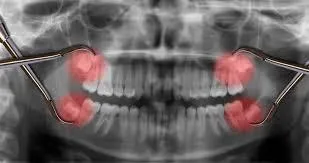

#10 - Wisdom Teeth Become Inflamed

Wisdom teeth are notoriously painful. They seem to come whenever they please, and when they do, they can easily wreak havoc. Pericoronitis is an infection that can occur when your wisdom teeth don’t come in properly. The risk of this spreading is too high to neglect.

If you get it, you’ll know because of your irritated gums in that area, as well as possible bad breath. You'll likely feel a painful pressure in your wisdom teeth area also. See a dentist as soon as possible to get this resolved.